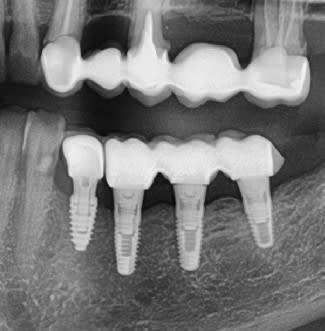

bonjour les experts

Pourriez vous me dire quel est le type d implant sur 35 36 37

en 34 c est du anyridge

C était du transvissée zircone et la céramique s est fracturée en plusieurs ,la vis du pilier multiunit est bleue et de gros diamètre j ai pu dévisser avec tournevis megagen

Bein tu peux recommencer et en profiter pour faire une bonne rétro et faire un export des radios via ton logiciel d’imagerie par ce que la photo au smarphone de la panoramique affichée sur l’écran, c’est de la merde on voit rien tellement c’est pixelisé…

c'est mieux.....mais pas suffisant

rétro pour avoir les détails de la connexion, tu type de spires, etc....

hexagone interne non conique